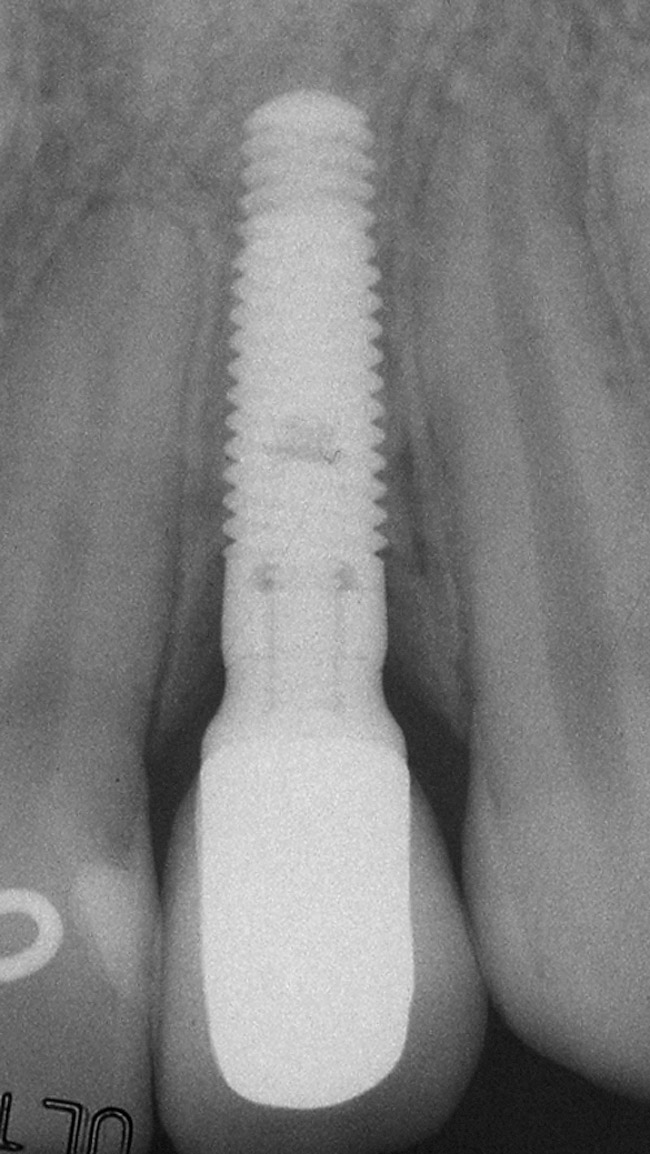

Figure 5h  Postoperative radiographs.

Figure 5h

Figure 5g  Postoperative radiographs.

Figure 5i